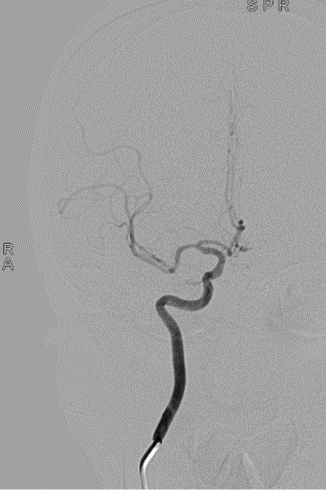

Wallstent 7-40mm颈动脉支架支架置入。

波科支架怎么样径技-弓上病例大赏|第205期·放疗后症状性颈动脉狭窄支架置入治疗一例_https://www.jmylbn.com_新闻资讯_第17张

波科支架怎么样径技-弓上病例大赏|第205期·放疗后症状性颈动脉狭窄支架置入治疗一例_https://www.jmylbn.com_新闻资讯_第18张

波科支架怎么样径技-弓上病例大赏|第205期·放疗后症状性颈动脉狭窄支架置入治疗一例_https://www.jmylbn.com_新闻资讯_第19张

总结

➢ 本例患者应用的波科保护伞(FilterWire EZ3.5mm-5.5mm)具有高捕获率及可靠的贴壁性能同时有良好的输送性,不用微导丝导引,操作过程中内膜损伤及产生夹层风险小并且回收简单。该患者术后保护伞回收后可见捕获的脱落斑块

➢ Wallstent颈动脉支架为闭环编织设计,具有高度的柔顺性,贴壁性更好,网眼密,斑块覆盖率高,术中显影好,半释放后仍可回收,便于定位,非常适合本病例血管不稳定斑块及术中夹层病变的血管治疗。